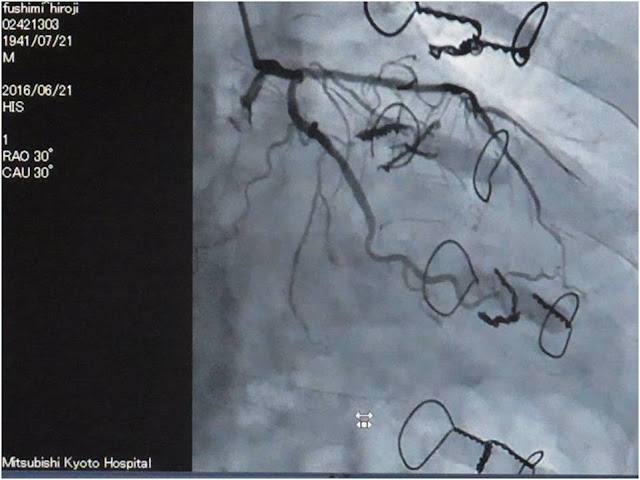

私事にわたるが、琵琶湖研究所の1988年の調査でケガをし、肋骨7本、鎖骨1本を折り、2ヶ月の入院を余儀なくされた。その際、肋骨4本が肺に刺さったので、肺の手術のため背中に30cm、加えて鎖骨周辺に10cm程の手術跡が残っている。その時以来、4本の肋骨には針金が巻かれている(P14)が、空港のX線検査では幸いひっかかったことはないし、このケガのおかげか、20年以上にわたる喫煙習慣ともおさらばすることができたのである。さらに、2014年には狭心症を再発し、3度の手術を行った結果、心臓の冠動脈にステントが9箇所に埋め込められ、血液がやっと流れるようになった(P14)。そのぼくも後期高齢者の仲間入りし、ヒマラヤを最初に訪れた20代の“青雲の志”は遠くになりにけりだが、樋口先生の「地球からの発想」にあやかり、せめて当時の“Passion・Mission・Action”の気概を想いだしながら、2015年の地震で大災害を受けたネパールにヒマラヤ地震博物館*とヒマラヤ災害情報センターを設立したい、とカトマンズ大学の講義のかたわら想っている。